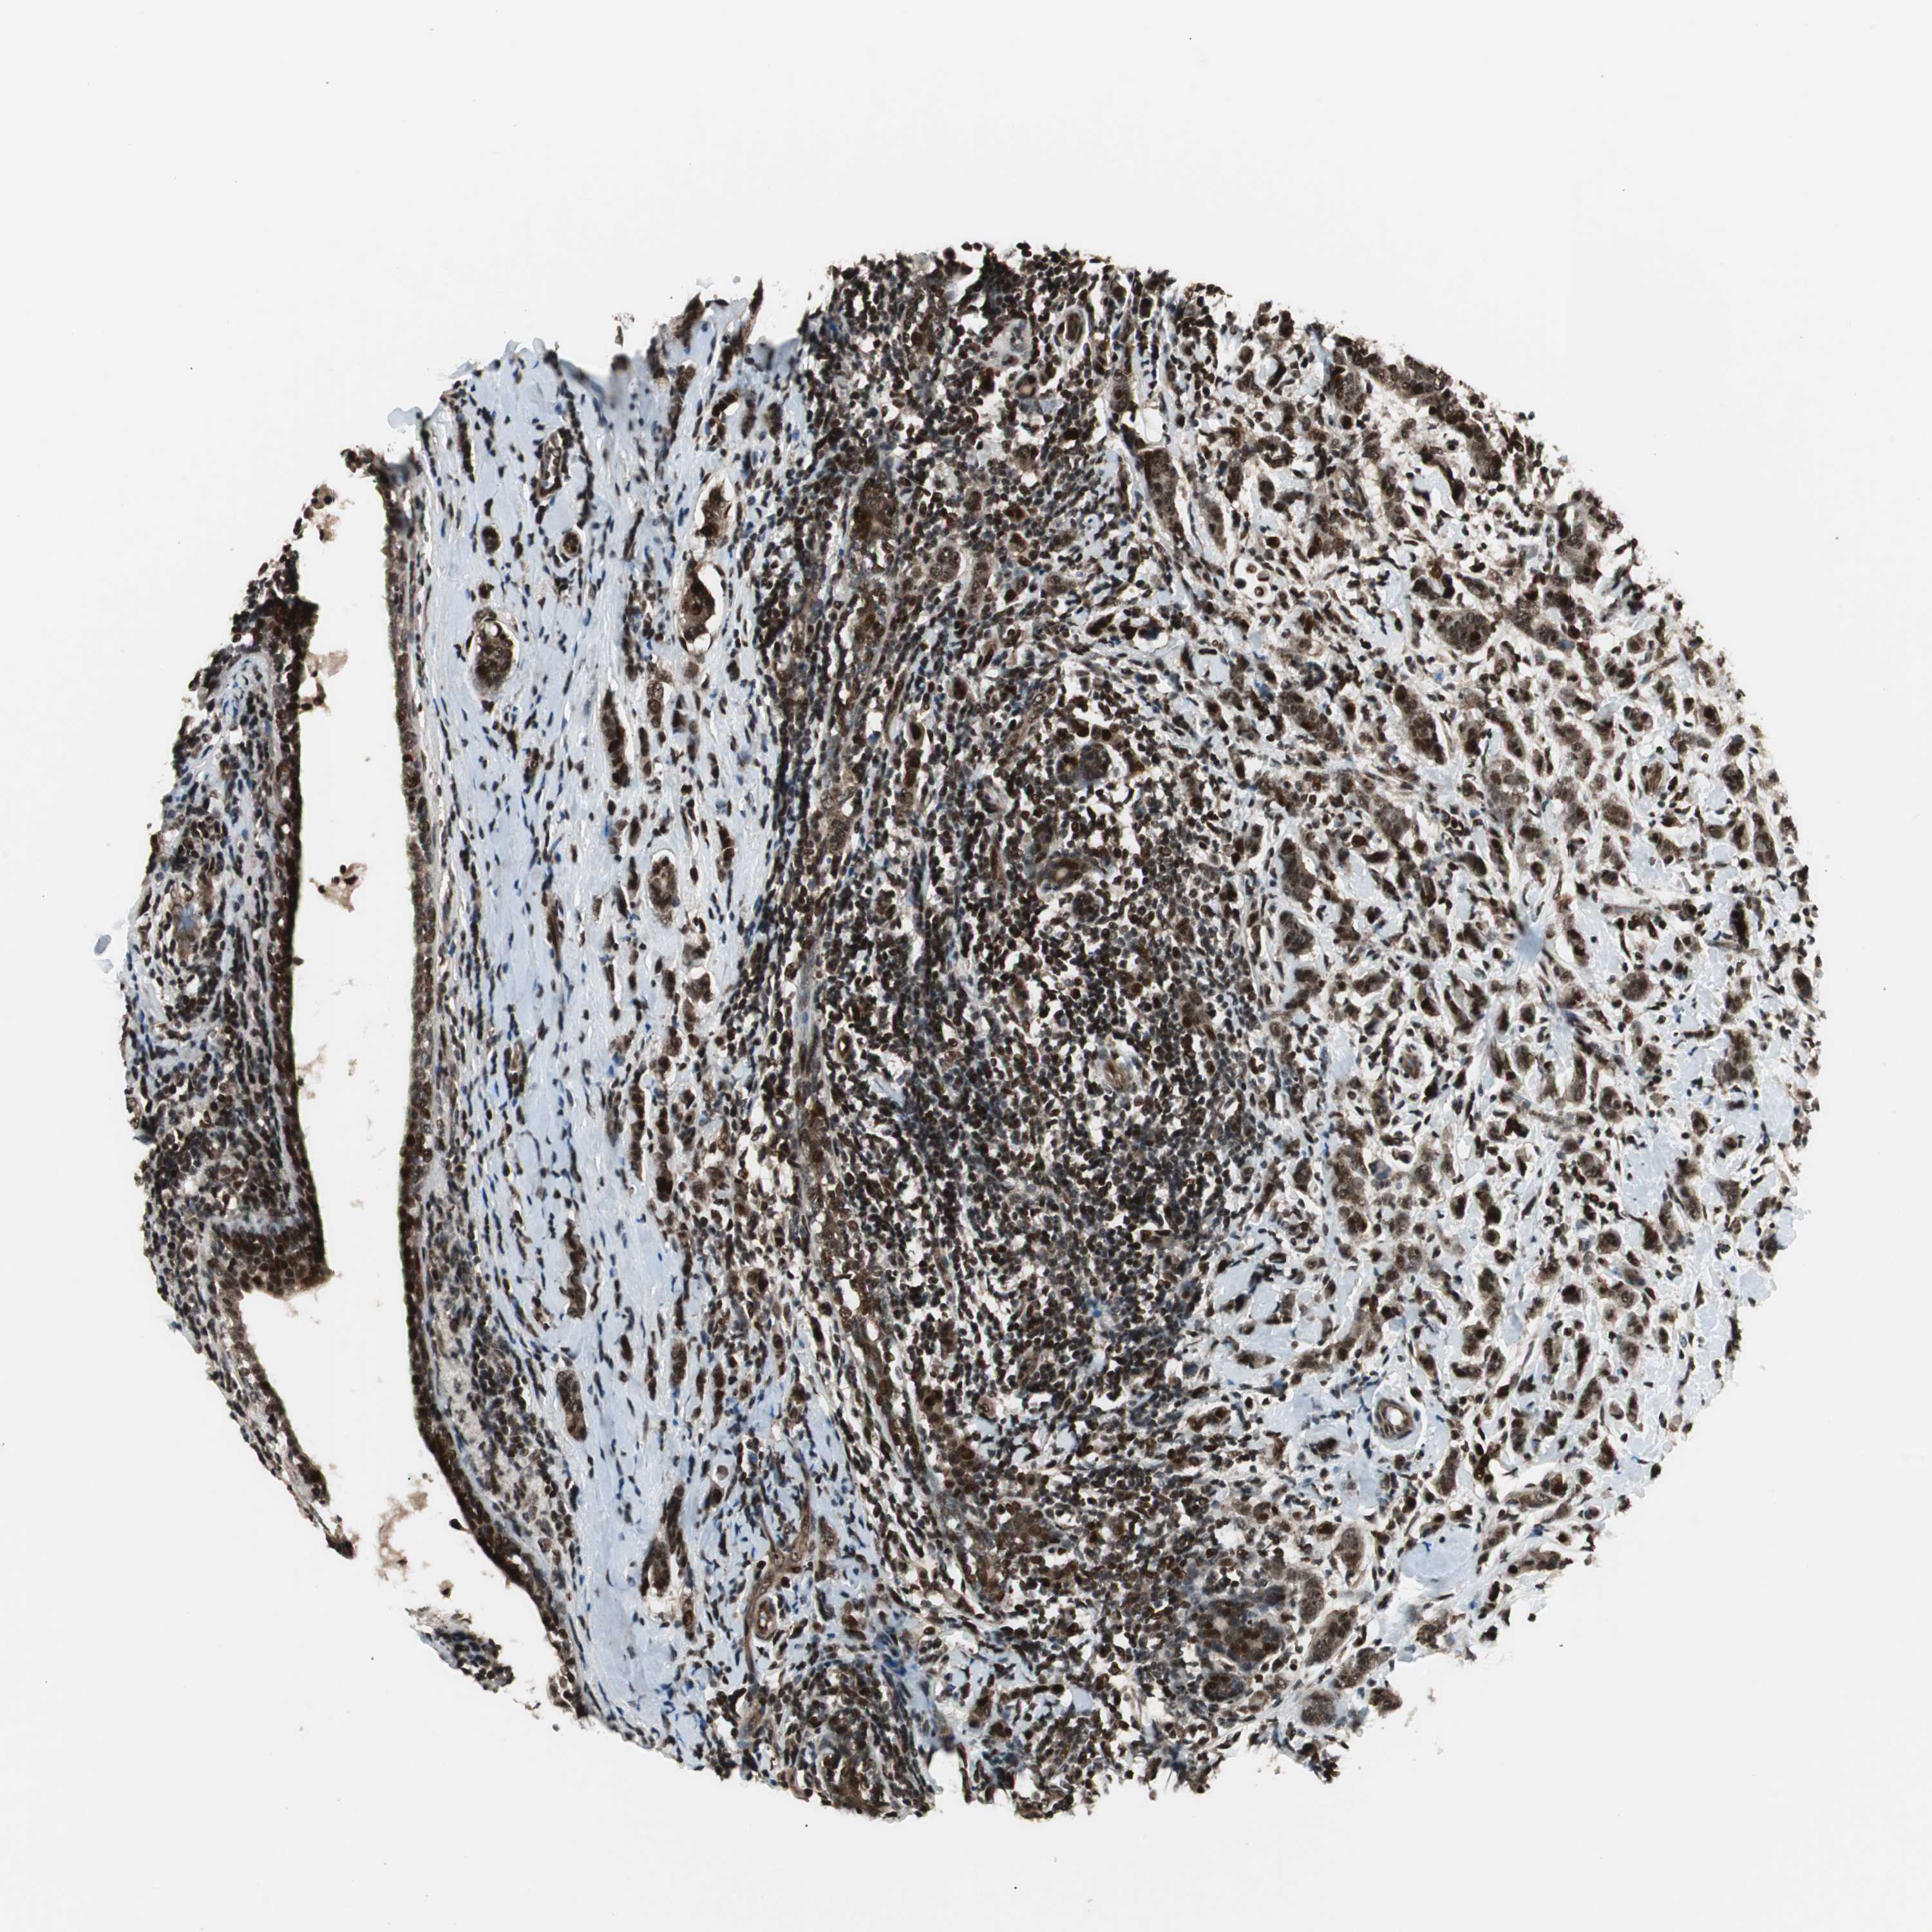

BRCA TCGA BRCA VALIDATION PROTEIN EXPRESSION